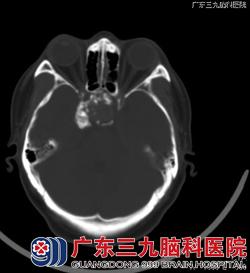

入院行CT及MRI检查:头颅CT平扫:蝶窦腔内及鞍上可见一不甚规则的占位性病变,病变部分边缘及内部可见多发斑片状钙化影,蝶窦窦壁骨质大部分吸收、破坏。MRI检查:鞍区、蝶窦区示一不规则团块状异常长T1短T2信号影,其内示散在斑点状等、稍短T1长T2异常信号影,部分边缘示斑条状T1WI更低信号影,呈不规则环形强化,范围约34.8mm×30.5mm×37.8mm,部分凸向鞍上,推移双侧颈内动脉海绵窦段,垂体显示不清。斜坡部分受压骨质吸收。术前影像诊断:考虑骨源性肿瘤。术后病理:组合型牙瘤。镜下见蝶窦内充满大量灰黄色沙粒样物,质软,血供不丰富,手术予以刮匙镜下全部刮除,可见蝶窦上方及岩斜处骨质破坏,硬脑膜完整,未见脑脊液流出。www.999brain.com

T2WI T1WI增强

广东三九脑科医院影像诊断中心汪文胜主任表示,本例特点:1.发生在蝶窦区,国内外未见有报道。病因考虑为牙源性上皮和间叶组织异位到蝶窦区所致。2.发病年龄偏大,但病人病史长达20年,是否为20年前就已经存在该病变,无法证实。3.关于牙瘤的MR或CT影像表现,国内相关文献未见有报道。本例影像特点:钙化特别多,蝶窦窦壁骨质大部分呈吸收改变,破坏相对较少,符合良性病变特点;T2WI以明显低信号为主,增强后,呈不规则环形强化。 www.999brain.com